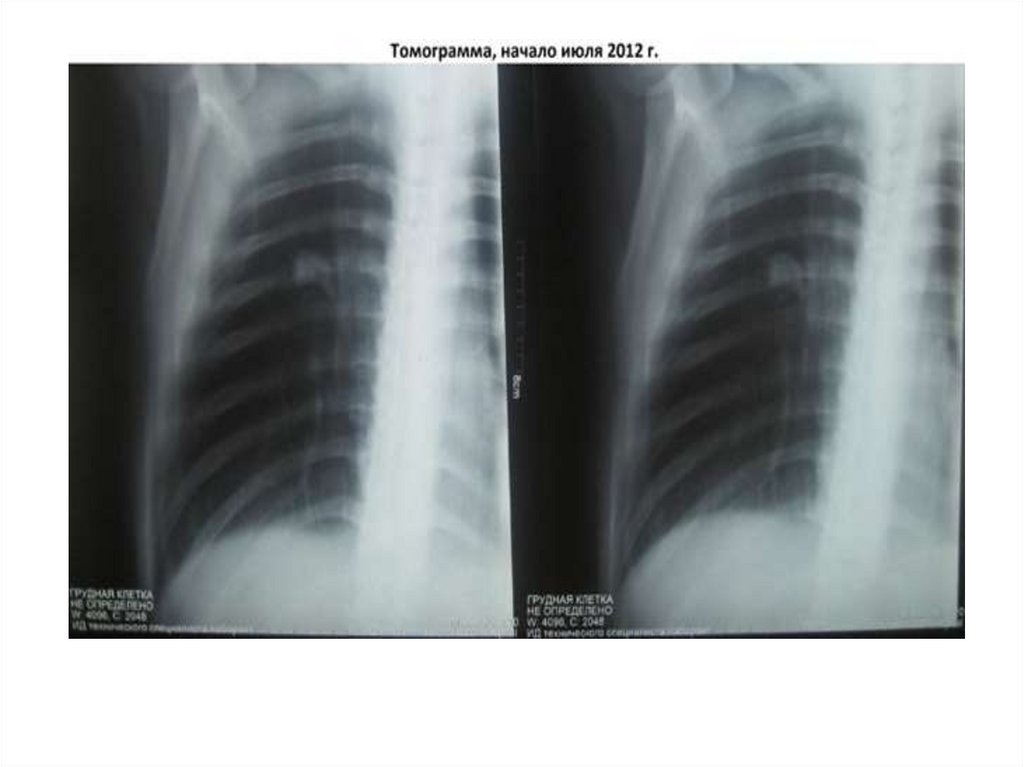

Рентгенограмма №1

30. Рентгенограмма №1